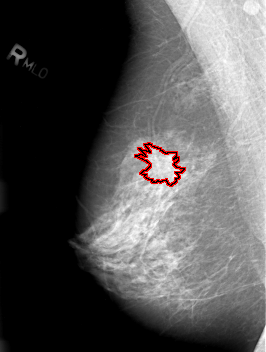

ics_version 1.0 filename B-3012-1 DATE_OF_STUDY 23 5 1995 PATIENT_AGE 53 FILM FILM_TYPE REGULAR DENSITY 3 DATE_DIGITIZED 24 4 1997 DIGITIZER LUMISYS LASER SEQUENCE LEFT_CC LINES 4256 PIXELS_PER_LINE 2752 BITS_PER_PIXEL 12 RESOLUTION 50 NON_OVERLAY LEFT_MLO LINES 4336 PIXELS_PER_LINE 2696 BITS_PER_PIXEL 12 RESOLUTION 50 NON_OVERLAY RIGHT_CC LINES 4136 PIXELS_PER_LINE 3152 BITS_PER_PIXEL 12 RESOLUTION 50 OVERLAY RIGHT_MLO LINES 4216 PIXELS_PER_LINE 3192 BITS_PER_PIXEL 12 RESOLUTION 50 OVERLAY |

FILE: B_3012_1.RIGHT_MLO.OVERLAY TOTAL_ABNORMALITIES 1 ABNORMALITY 1 LESION_TYPE MASS SHAPE IRREGULAR MARGINS SPICULATED ASSESSMENT 4 SUBTLETY 3 PATHOLOGY MALIGNANT TOTAL_OUTLINES 1 BOUNDARY |